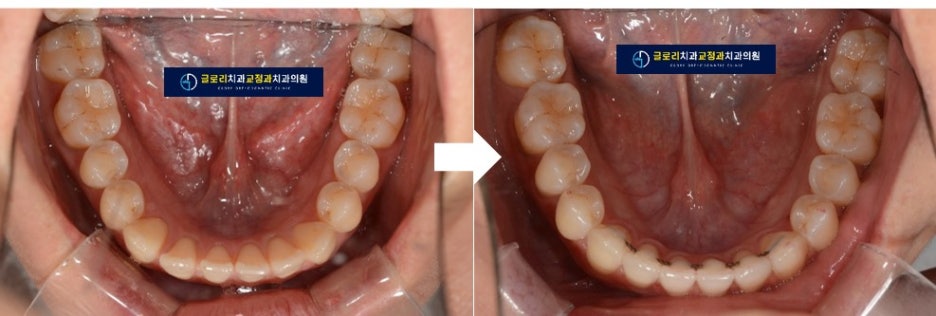

2) 교합면 사진

교합면에서도 어금니쪽은 촘촘하게 치아들이 붙어있지만

앞니쪽은 공간이 많이 있는 것을 알 수 있습니다.